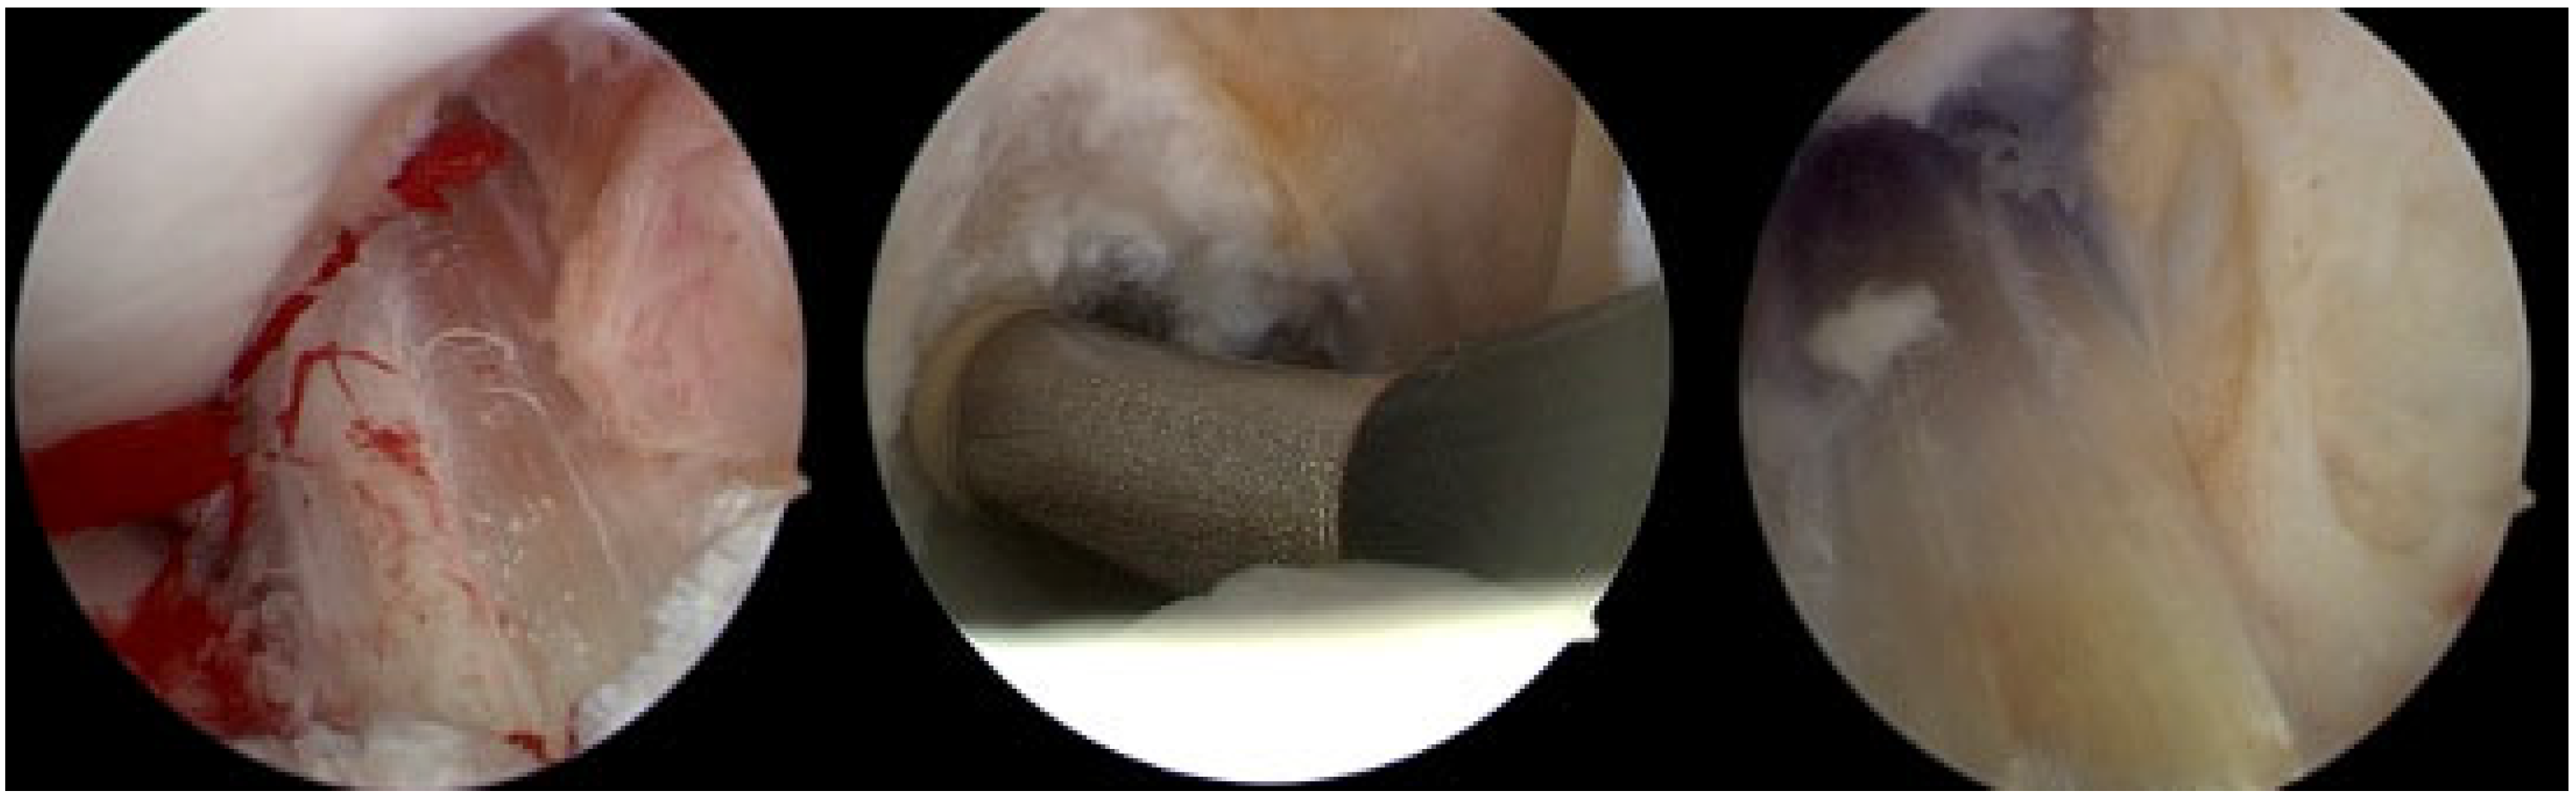

Arthroscopic Anterior Cuciate Ligament Reconstruction Using Neither a Tourniquet nor Drainage: A Perioperative Case Series Report

2. Materials and Methods